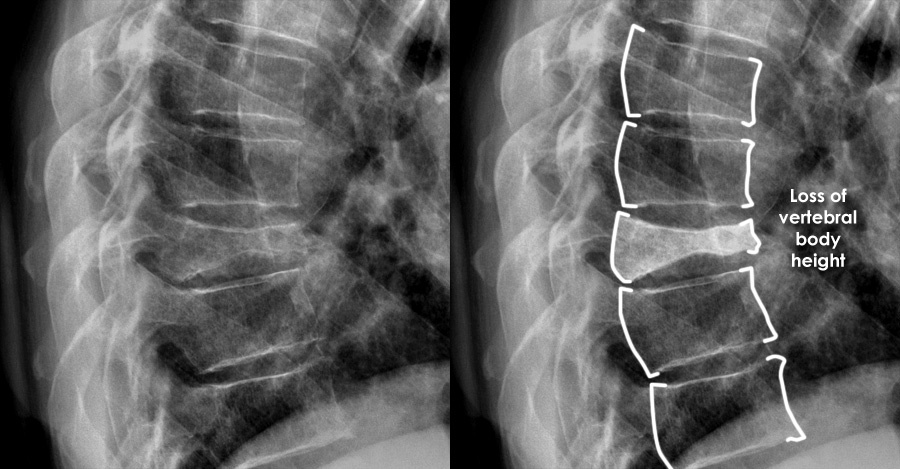

Взято из открытых источников.  Значительно уменьшена высота тела одного из позвонков с клиновидной его деформацией. Это компрессионный перелом  грудного позвонка

Болезнь эта тихая, но последствия просто оглушительные - инвалидизация из-за перелома шейки бедра или позвоночника. Остеопороз не болит, поэтому о его существовании обычно сам человек не догадывается. Почему-то юбки или брюки стали длиннее (если рост человека за жизнь уменьшился на 4 см , то это уже признак остеопороза). Или осанка поменялась и родственники постоянно делают замечание: «Мама, прекрати сутулиться!». Спина стала быстрее уставать, живот стал выпячиваться, руки как-будто стали длиннее - всё это уже симптомы остеопоретических компрессионных переломов позвонков, далеко зашедшего остеопороза. Таких пациентов видно сразу при появлении на пороге кабинета. Но при разговоре, что всё это последствия компрессионного перелома позвонков, я вижу в глазах пациентов абсолютное недоверие и непонимание. «Что вы доктор, я с лестницы не падала и на горных лыжах не каталась! Какой перелом?».

Патологические переломы на фоне остеопороза могут возникать при падении дома, запнувшись об шнур удлинителя, неловком движении, кашле, чихании и вообще без всякой видимой травмы. Есть пациенты, которые получают такие переломы, просто наклонившись завязать шнурок. Сильной боли может и не быть. Тем более, если у человека часто болит спина, и он уже не воспринимает эту боль, как сигнал тревоги.